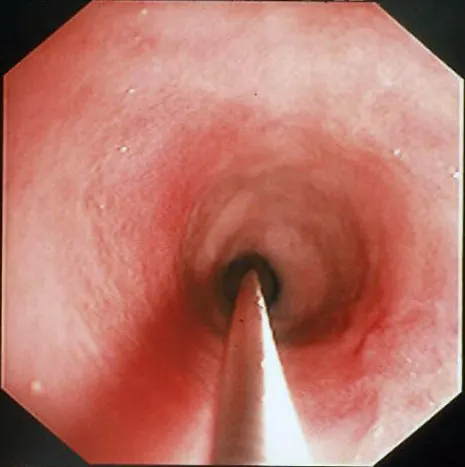

Normal colonic mucosa is pale pink, smooth, and glistening. Submucosal blood vessels are readily observed with adequate insufflation in dogs. Lymphoid aggregates, 2 to 3 mm in diameter and umbilicated, are most common within the rectum and cecum. Visual inspection of the cecum and ileocolic sphincter should be performed in all patients undergoing full colonoscopy. Parasitism, cecal inversion, ileocolic intussusception, inflammatory bowel disease, and neoplasia may cause mucosal lesions in this region.

Retrograde ileoscopy should be performed as part of routine lower GI endoscopic examination in large dogs; it is contraindicated in small dogs and cats because it may cause too much trauma. This procedure is useful when an insufficient quantity or poor-quality duodenal biopsy samples have been obtained. It necessitates thorough colonic cleansing and advancement of the endoscope tip through the ileocecal sphincter in dogs (A).